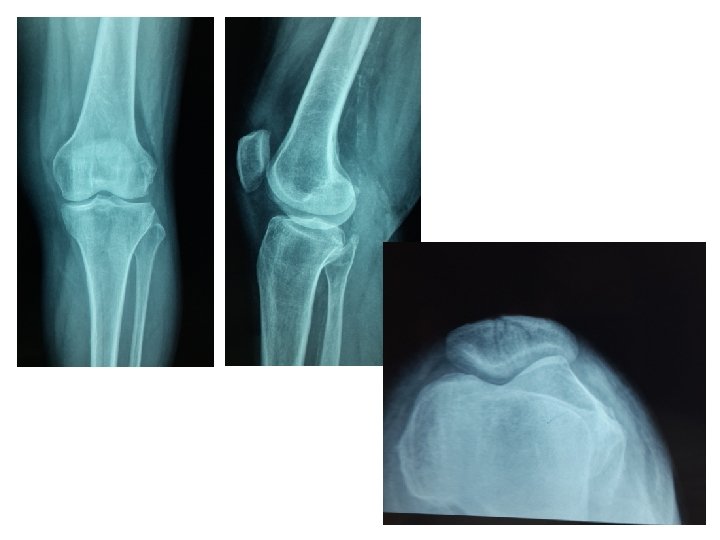

RADIOLOGIE • pose le diagnostic • permet la classification • recherche les lésions associées Rx du genou Face, profil Fracture comminutive

L’incidence fémoro-patellaire difficile à réaliser du fait des douleurs permet de voir les fractures sagittales

Fracture transversale